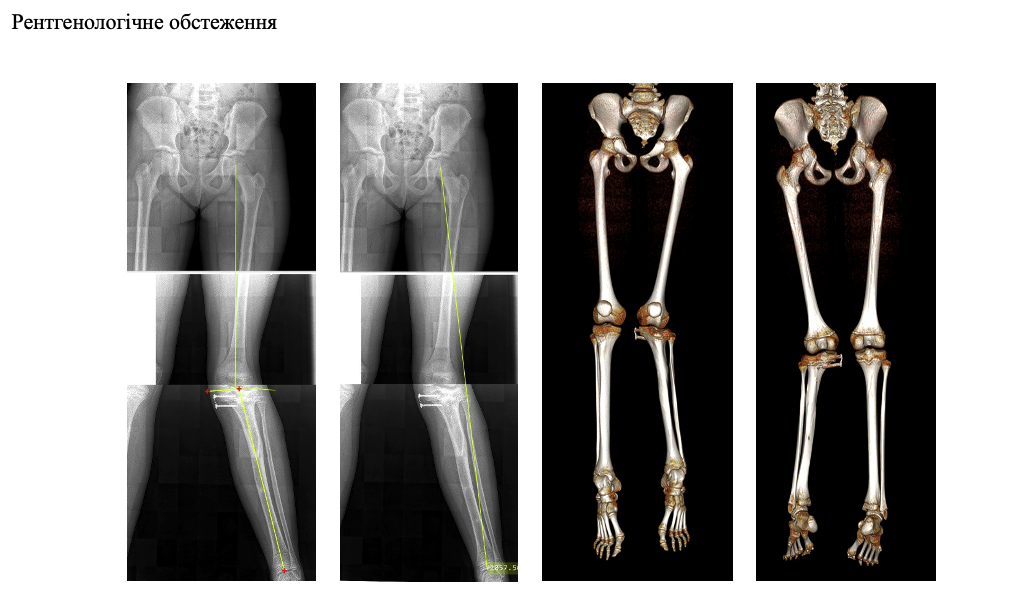

Повна діагностика: коли важлива кожна деталь

У лікарні «Експерт» дитині провели розширене обстеження опорно-рухового апарату. Виконано панорамну рентгенографію нижніх кінцівок із можливістю оцінки осі та довжини, рентгенометрію для точного визначення всіх компонентів деформації, ангіоКТ нижніх кінцівок для контролю судин та анатомічних особливостей, а також денситометрію для оцінки якості кісткової тканини.

На основі цих даних команда ортопедів сформувала детальний план реконструктивної операції з використанням сучасних систем зовнішньої фіксації та фіксуючих елементів, що дозволяють поетапно відновити правильну вісь гомілки, стабільність суглобів і довжину кінцівки.